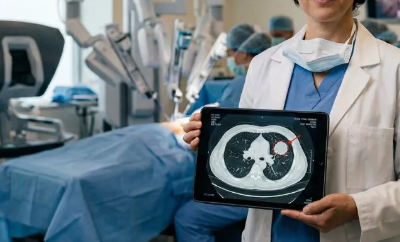

Lung Cancer

Lung cancer is one of the most common cancers in the world. We get the best results with video-assisted thoracoscopic surgery (VATS) or robotic-assisted thoracoscopic surgery (RATS).